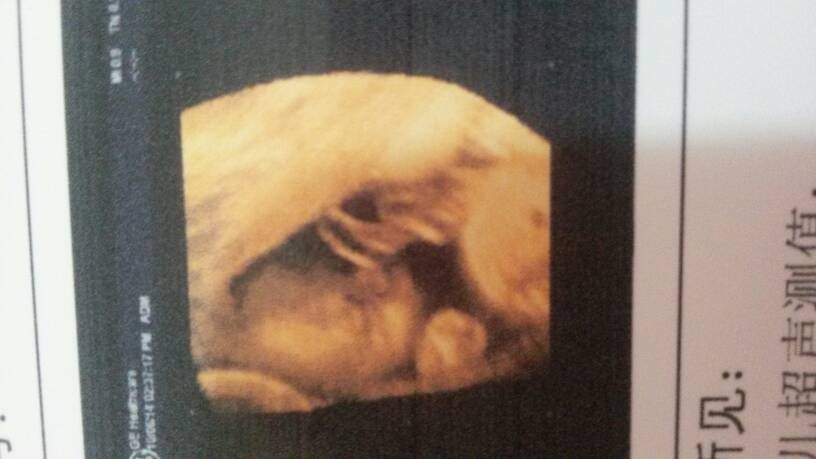

思维彩超 成功归来,接健康美宝宝~ 思维彩超 成功归来,接健康美宝宝~ 点击展开 不想长大. 2014-10-08 12:23 为您推荐: 其他回答 接下来自己还是要安排好孕期的基本检查:32周心脏彩超、36周做全面彩超(监视胎儿的生育情况)36周后,每周做一次胎监。 群岛舟山 2014-10-09 12:04 祝福你,,, 为了爱,为了宝 2014-10-08 13:31 祝福你 宝妈 天使泪_K1vV 2014-10-08 12:54 恭喜宝妈! ザ冰封的心ヽ 2014-10-08 12:41 恭喜恭喜宝妈 丶半世浮殇 2014-10-08 12:29 加载更多 相关问题 几个月的时候可以拍思维彩超看到宝宝健康不健康呢 三级彩超归来,医生说胎儿有问题,我真的不想就这样结束一条生命,我特希望她能健康地来到我身边,我想再 思维彩超主要是查胎儿什么的呢?